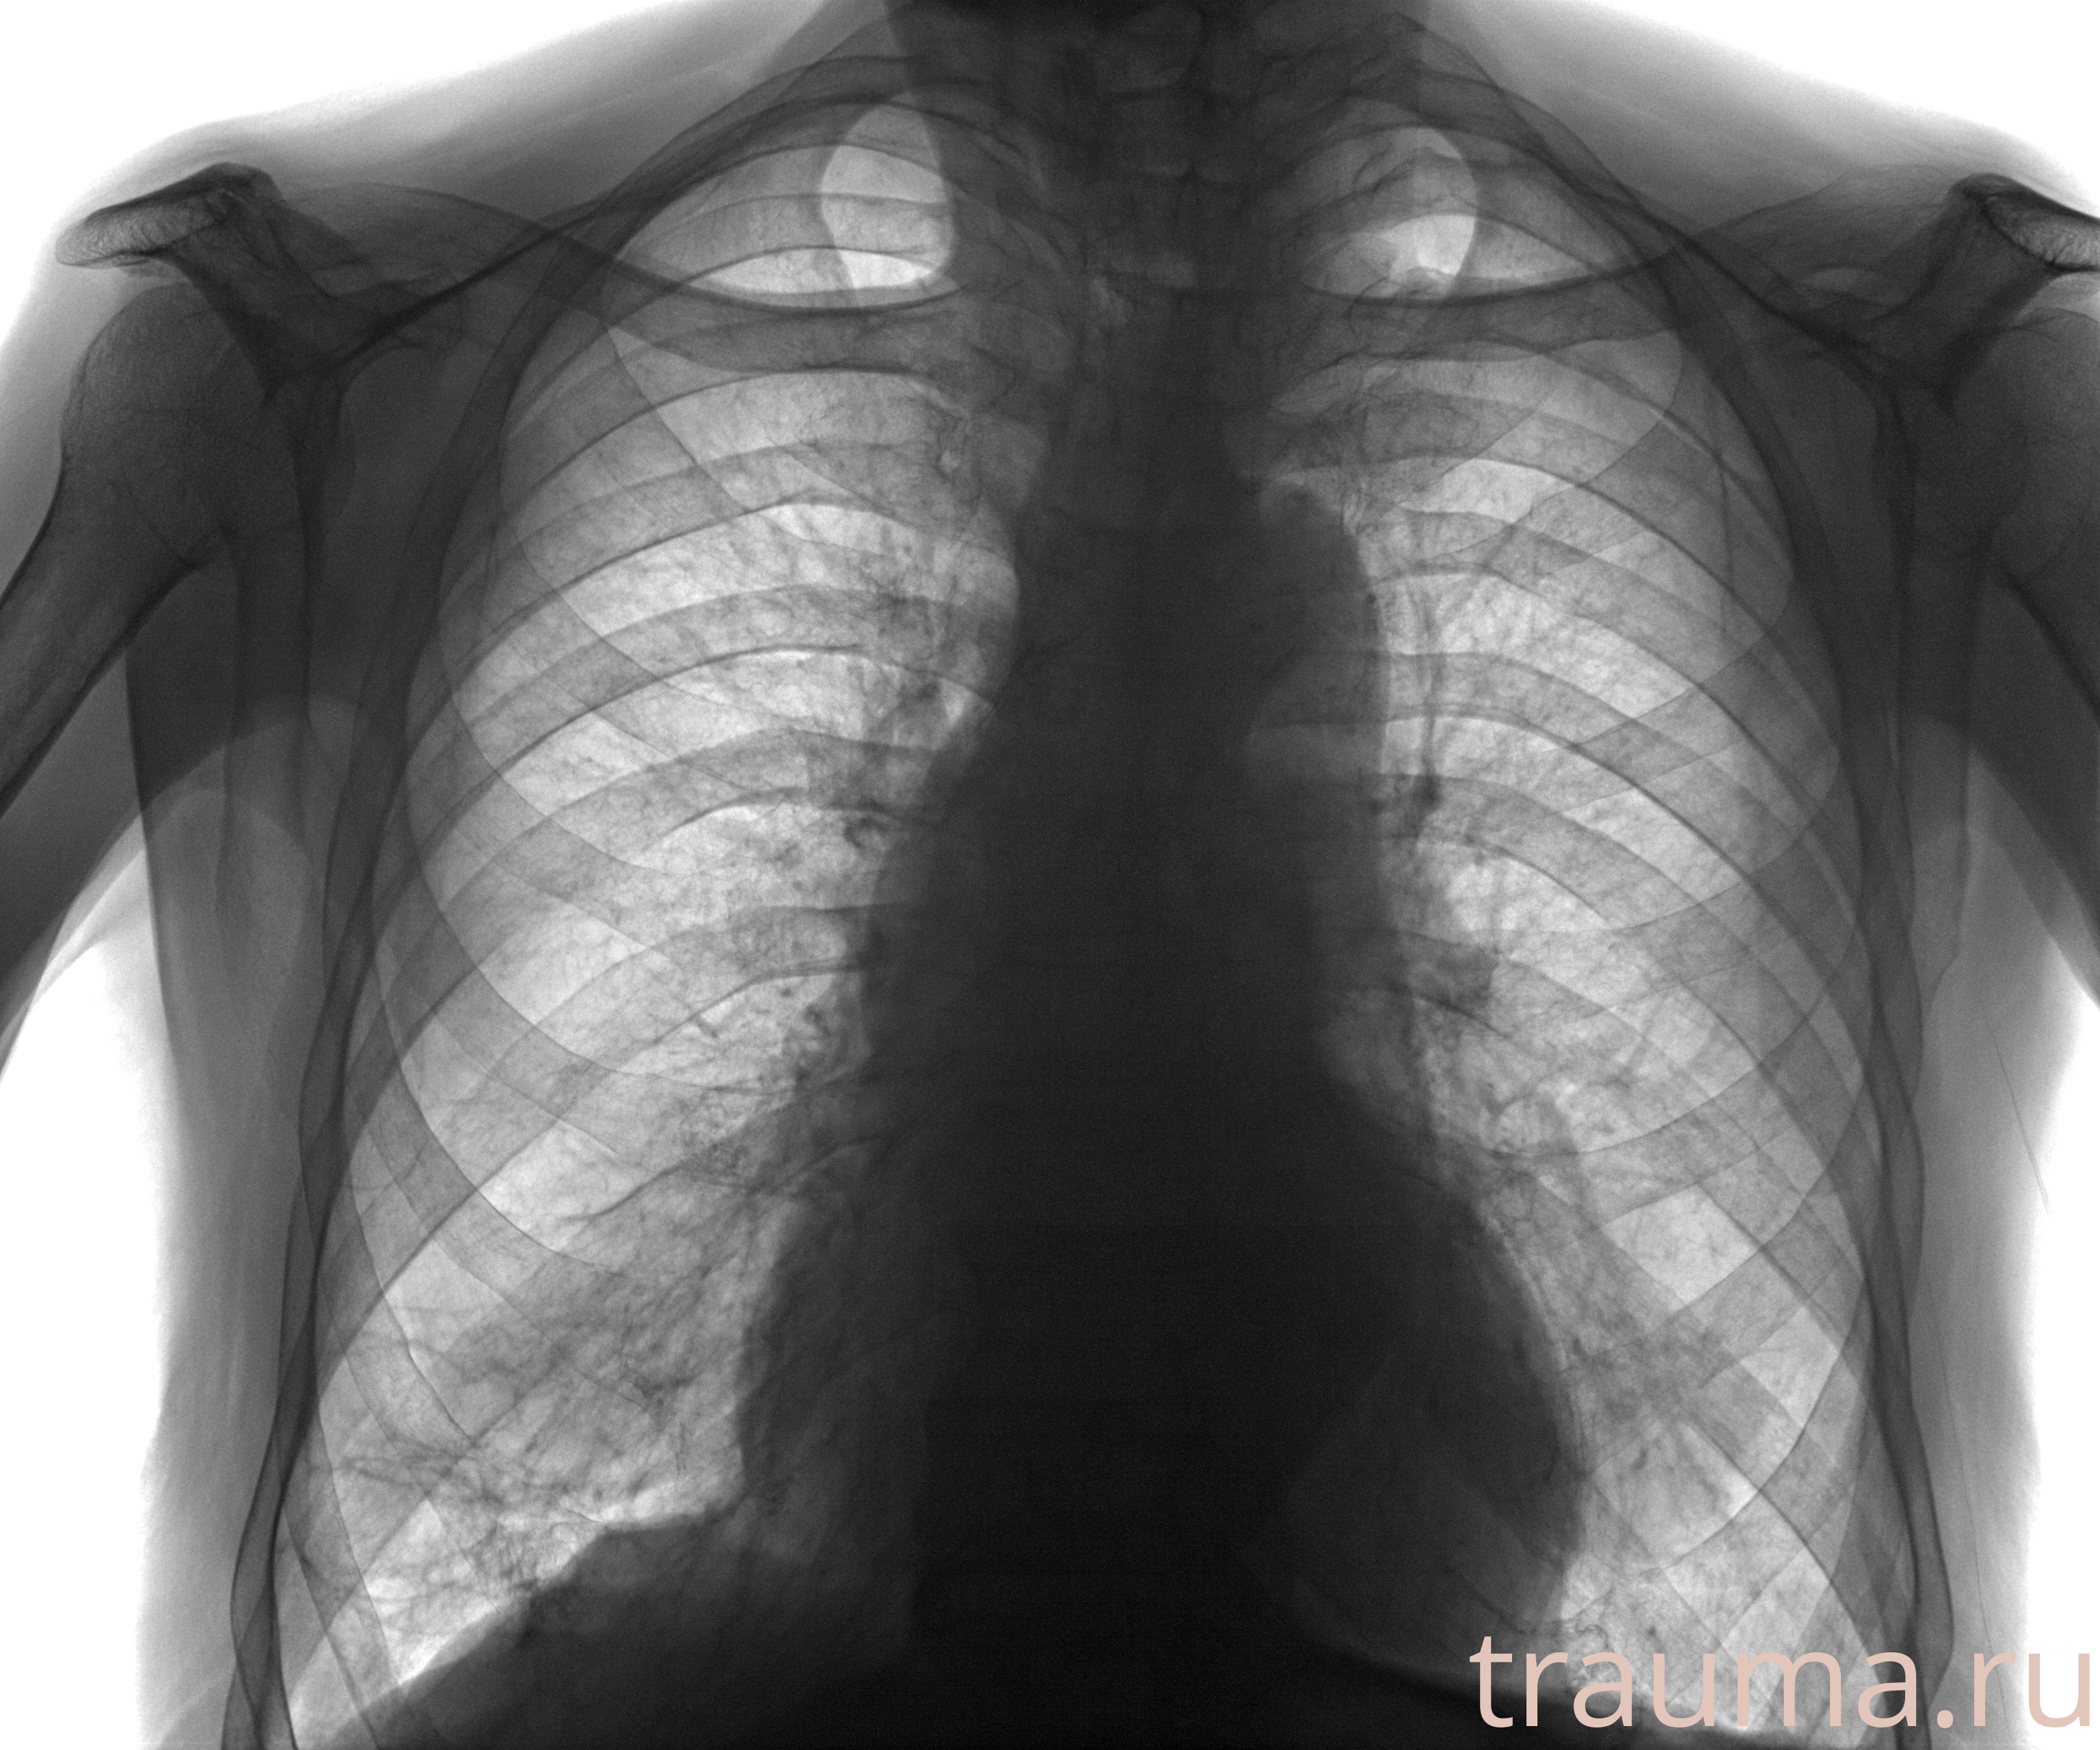

Рентген на дому: по вашему адресу приезжает врач-рентгенолог, травматолог-ортопед с мобильным рентгеновским аппаратом, проводит диагностику травмы или заболевания, делает необходимые рентгенограммы, дает рекомендации по дальнейшему лечению. Получить качественные снимки в домашних условиях возможно благодаря уникальной методике, разработанной МосРентген Центром для института  Склифосовского

при переломе шейки бедра и пневмонии от компании МосРентген Центр - партнера Института имени Склифосовского